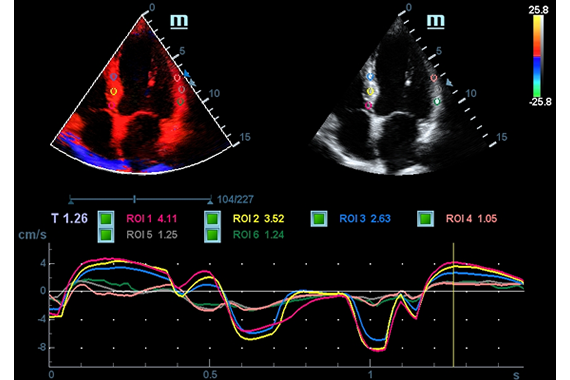

Клинические изображения

- TDI (Tissue Doppler imaging, including TDI Color, Power, PW and M mode) - пакет тканевой допплерографии, включая цветное картирование, импульсный тканевой допплер, энергетический тканевой допплер и тканевой М-режим

- TDI Quantification Analysis Software - количественный анализ тканевого допплера (необходима опция TDI)